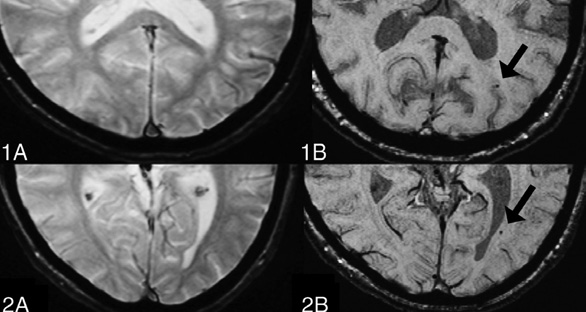

Figure 2. (Adapted from Shams S, Martola J, Cavallin L, et al. SWI or T2*: Which MRI Sequence to Use in the Detection of Cerebral Microbleeds? The Karolinska Imaging Dementia Study [8]). 1A and 2A present the T2* sequence, while 1B and 2B present the tSWI sequence. CMBs are visible on tSWI but not on T2*, demonstrating the greater sensitivity of SWI to CMBs.

SWI is particularly effective for visualizing cerebral microbleeds due to several key technical advantages [7]. Unlike the two-dimensional (2D) Gradient Recalled Echo (GRE) approach, SWI is acquired as a 3D sequence, allowing for thinner slices and smaller voxel sizes, which enhances the spatial resolution and provides a more detailed view of the brain structures. This enables SWI to detect small lesions and subtle vascular abnormalities that GRE might miss. Furthermore, SWI incorporates flow compensation across all three dimensions (x, y, and z), thereby significantly reducing artifacts from the blood flow and patient movement, resulting in clearer and more accurate imaging. Another major advantage is that SWI captures both magnitude and phase information, allowing these to be processed independently or together to enhance the contrast and detect subtle magnetic susceptibility changes, such as microbleeds or iron deposits. In contrast, GRE does not fully utilize the phase data, making it less effective for identifying such subtle abnormalities [8]. Studies also support the superiority of SWI over GRE, by highlighting its enhanced sensitivity and accuracy in detecting subtle brain abnormalities. Research conducted by Tong et al. [9] and Babikian et al. [10] has demonstrated that SWI is three to six times more effective than the standard T2*-weighted gradient-echo sequences in visualizing the size, number, volume, and distribution of hemorrhagic lesions. Furthermore, it is observed that microbleeds could be detected long time after the injury and remain unchanged for at least 100 days following the injury on in vivo MRI scans [11]. However, in the acute phase, microbleeds are not static, but, instead, they change in number and volume over time. Consequently, the timing of imaging is essential for optimizing the prognostic value of SWI. The distinct biophysical characteristics of microbleeds lead to a temporary alignment in intensity with the surrounding white matter on imaging, which can obscure their visibility within 24 to 72 hours after the injury. This temporary decrease in detectability underscores the necessity of accounting for the time elapsed since the trauma when interpreting SWI findings. During this period, an apparent absence or reduction in the number of microbleeds may not accurately represent the true extent of the injury [12].